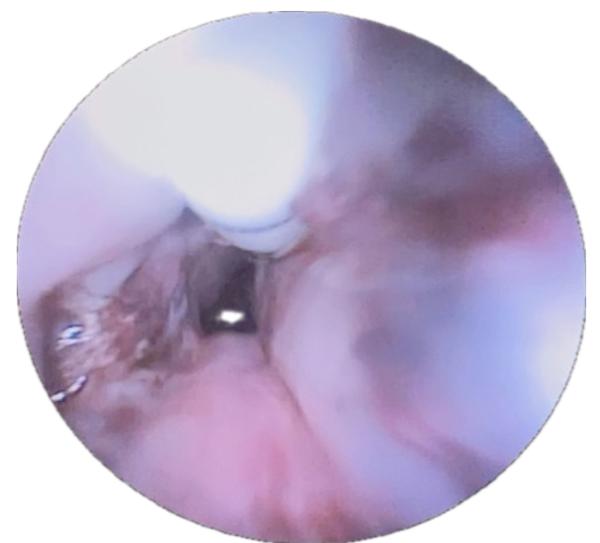

Endoscopia (EVDA) diagnóstica identifica cuerpo extraño lineal de 3 cm enclavado en pared posterior cervical.

Identificación endoscópica de cuerpo extraño

EVDA muestra objeto lineal de 3 cm enclavado sobre pared posterior cervical, hallazgo concordante con la clínica de disfagia prolongada; la endoscopia es el método de elección para diagnóstico/tratamiento de cuerpos extraños esofágicos en pediatría.

ENDOSCOPIA es clave para diagnosticar y retirar cuerpos extraños y para verificar la estanqueidad posoperatoria